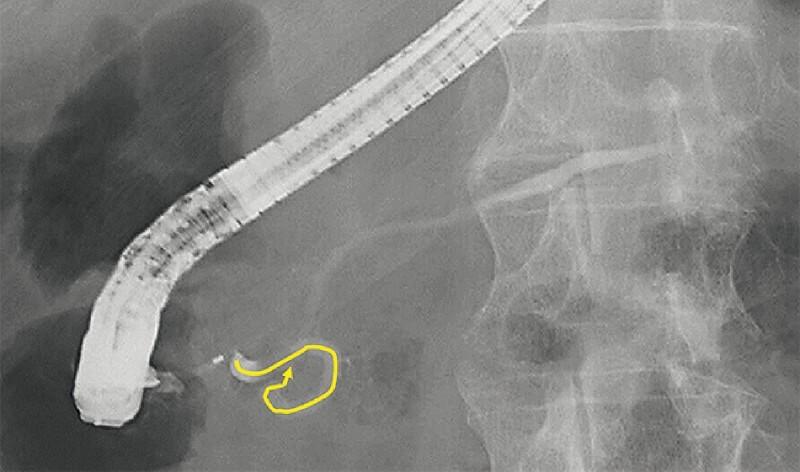

Mandai Koichiro, Shinomiya Ryo

Department of Gastroenterology, Kyoto Second Red Cross Hospital, Kyoto, Japan.

Endoscopy. 2022 Dec;54(S 02):E1051-E1052. doi: 10.1055/a-1913-7425. Epub 2022 Aug 25.